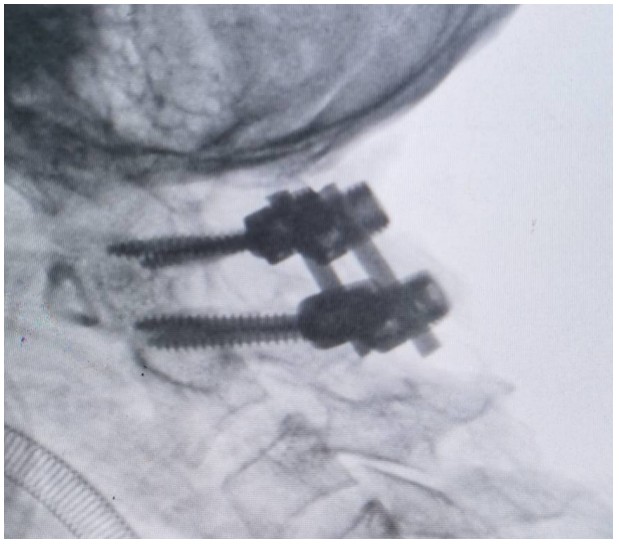

術(shù)中,錢軍博士團(tuán)隊(duì)展現(xiàn)出了非凡的勇氣和精湛的醫(yī)術(shù)。他們精心準(zhǔn)備,與手術(shù)室和麻醉科的同仁們緊密協(xié)作,以專業(yè)的技術(shù)和精確的操作,成功完成了這一高難度的手術(shù)。手術(shù)室外,譚女士的家人焦急等待,當(dāng)手術(shù)成功的消息傳來時,譚女士的家人不禁流下了感激的淚水。

術(shù)后,譚女士在骨科一區(qū)(脊柱外科)醫(yī)護(hù)人員的細(xì)心照料下,逐漸恢復(fù)活力,痛苦得到緩解,頸椎活動也日益靈活。譚女士的家屬對手術(shù)效果感到非常滿意,多次對醫(yī)護(hù)人員的精湛技藝和無私奉獻(xiàn),當(dāng)面表達(dá)出深深的敬意和感激。